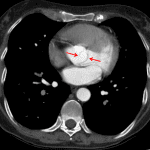

Indication: Chest pain, history of bicuspid aortic valve

- Ascending aortic aneurysm measuring up to 5.1 cm

- Normal aortic diameter in the arch and at the sinotubular junction

- No dissection

- Fishmouth configuration of the aortic valve

- Subendocardial hypodensity at the left ventricular apex

- Ascending aortic aneurysm

Ascending aortic aneurysm measuring up to 5.1 cm in diameter without aneurysmal dilation of the aortic arch or sinotubular junction.

Fishmouth configuration of the aortic valve consistent with known bicuspid aortic valve.